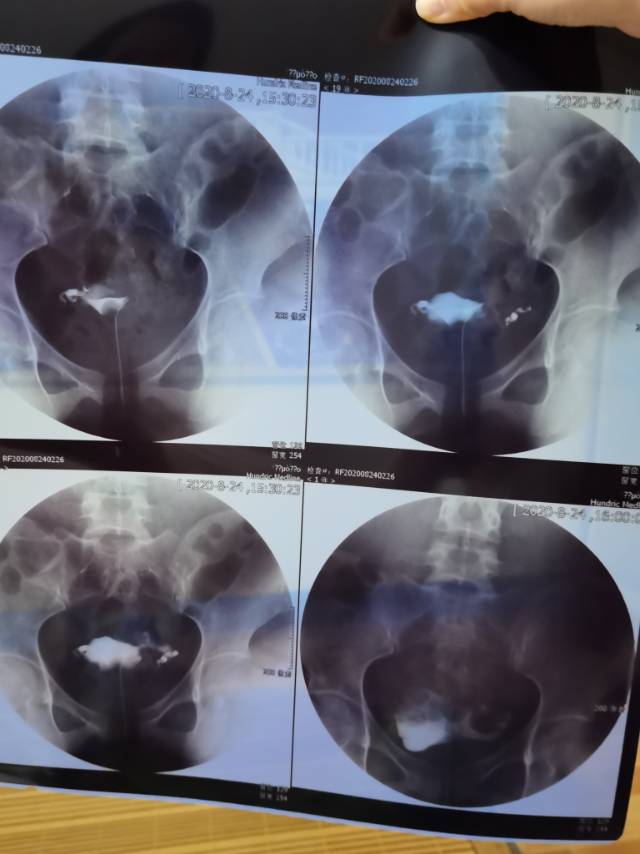

做完输卵管造影第六天了小腹还是感觉沉甸甸的如

可以热敷腹部,如果有发热,腹痛加剧,白带量多,有异味,随时就医

刘翠荣

5位已回答